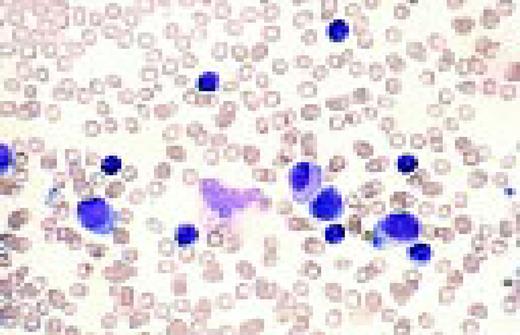

Slide L28

Reactive plasmacytosis with circulating plasma cells. Composite: blood (L) and bone marrow (R). This 71-year-old male was admitted because of fever (38.3°C) and suspected cholangitis. The WBC was 15.4 × 109/L with 10% plasma cells. A bone marrow aspirate showed about 30% small plasma cells with deep blue cytoplasm. A diagnosis of multiple myeloma with circulating plasma cells was considered. The total protein was not increased. The gamma globulin fraction was 40%. Agar electrophoresis revealed several monoclonal components. In the immunoelectrophoresis, the major component appeared to be a IgM-kappa paraprotein. The normal immunoglobulins were not decreased. Immunophenotyping of the blood plasma cells proved the polyclonality of these cells with a kappa/lambda ratio of 55/45. After treatment of the infection, plasma cells disappeared from the blood.FIG28